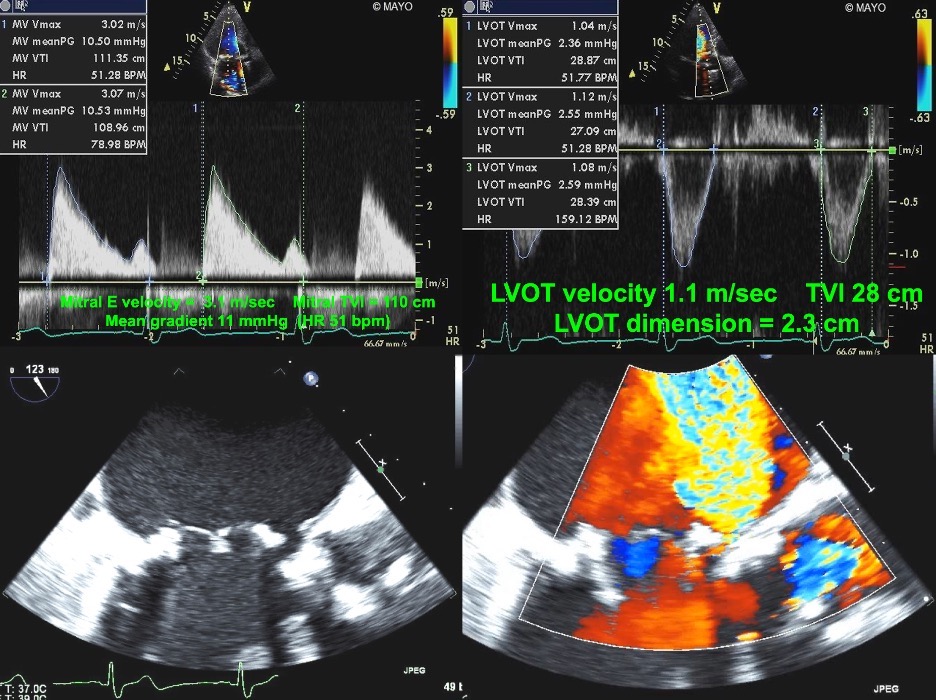

Fig. 7.Echocardiographic imaging of a patient with a mitral bioprosthesis and heart failure symptoms found to have prosthetic thrombosis.

Top Left: Continuous Wave Doppler in a patient with a

31 mm Hancock porcine mitral bioprosthesis who presented with dyspnea on exertion

and lightheadedness. The mean gradient was 12 mmHg with a heart rate of 51 and a

pressure halftime of 280 msec. The DVI was 5.7, with an EOAi of 0.44

cm